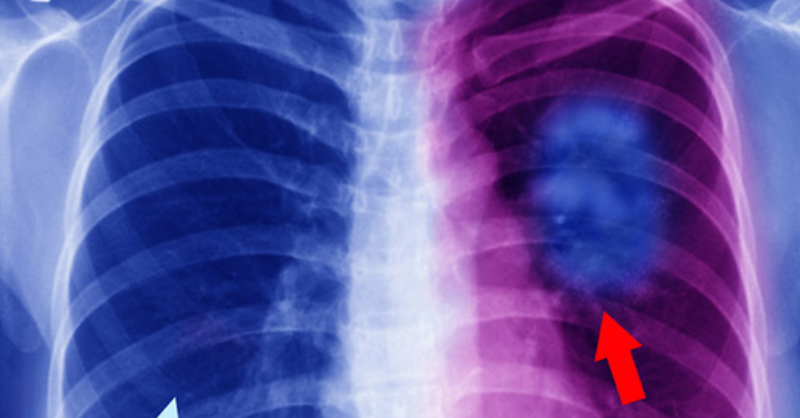

20 Early Warning Signs of Lung Cancer That People Should Never Ignore

Lung cancer is the second most common type of cancer in both men and women. In men, prostate cancer is the most prevalent, while in women, breast cancer...